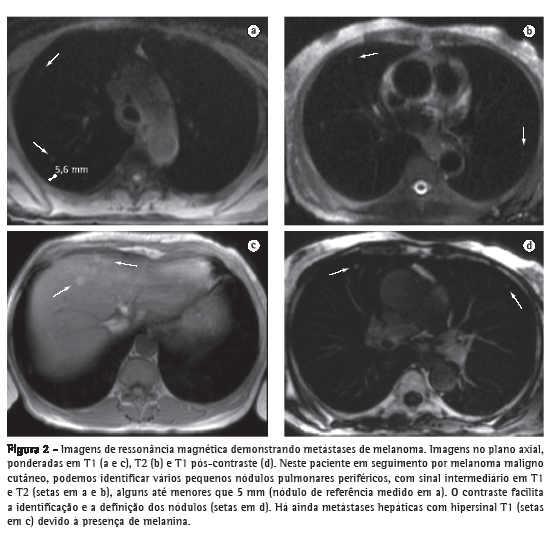

A RM na detecção de nódulos maiores que 4-5 mm tem acurácia superior à radiografia simples, e possui valores de especificidade e sensibilidade que chegam a 93%, quando comparados aos da TC de multidetectores.(18) A sensibilidade está diretamente relacionada ao tamanho do nódulo, sendo mais baixa para nódulos menores que 5 mm, mas chegando próximo a 100% na detecção de nódulos iguais ou maiores que 10 mm (Figura 2). Dessa maneira, principalmente com as sequências HASTE e GE 3D, a RM pulmonar deve ser utilizada para complementar estudos cardíacos, de lesões mediastinais ou da parede torácica, ou mesmo como uma alternativa à TC na pesquisa de metástases pulmonares. As principais limitações da RM no estudo das lesões focais pulmonares são, principalmente, nos casos de lesões calcificadas e na detecção da linfangite carcinomatosa.(18-20)